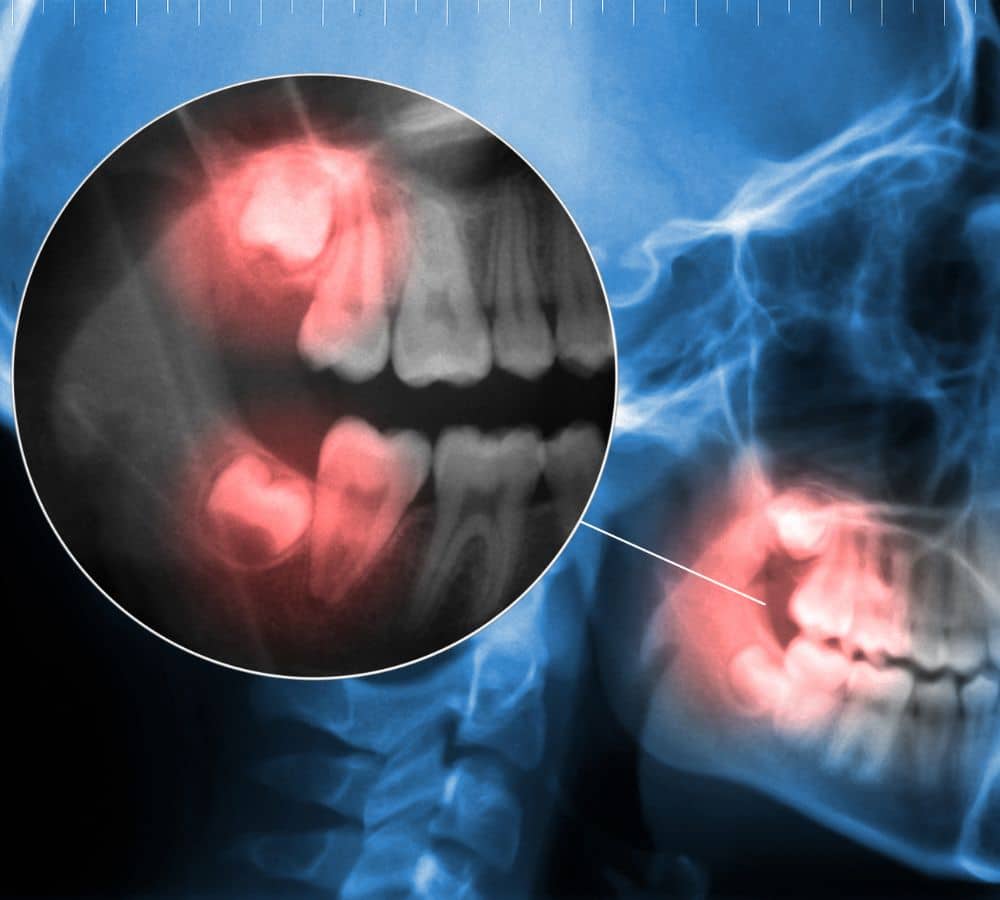

Because wisdom teeth are the last teeth to erupt into the jaw, they often struggle for space and this can cause them to become impacted, or remain below the gum line. When wisdom teeth are impacted, they can cause infection or decay in the teeth next to them.

A tooth that has only partially erupted or has come through at a crooked angle is known “impacted”. The gum around the impacted tooth may become swollen, painful or (in some cases) infected, which can cause considerable pain.

Wisdom teeth can erupt in lots of different positions, with differing levels of complexity associated with their removal. They can even be buried deep in the jawbone or in close proximity to facial structures such as nerves or sinuses.

At your first visit a clinical assessment of your wisdom teeth will be carried out. Normally a specialised X-ray called an OPG, or in more complex cases a three-dimensional scan called a CBCT, is arranged. This will give your clinician a better indication of where your wisdom teeth are placed in your jaw, and she or he will then be able to give you a clear picture of what to expect during and after extraction. The options for how the wisdom teeth are removed will be discussed in detail and of course your personal preferences will be taken into account.